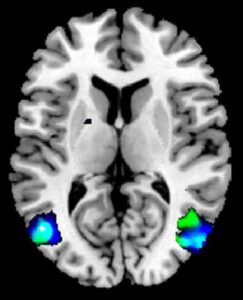

Meno materia grigia nelle aree del cervello coinvolte nella rappresentazione mentale di sé e nella manipolazione delle immagini. E' questa...